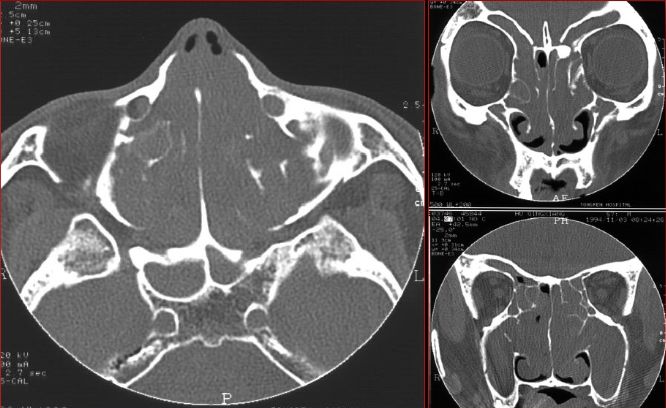

慢性多发鼻窦炎鼻息肉

慢性多发鼻窦炎—MRI